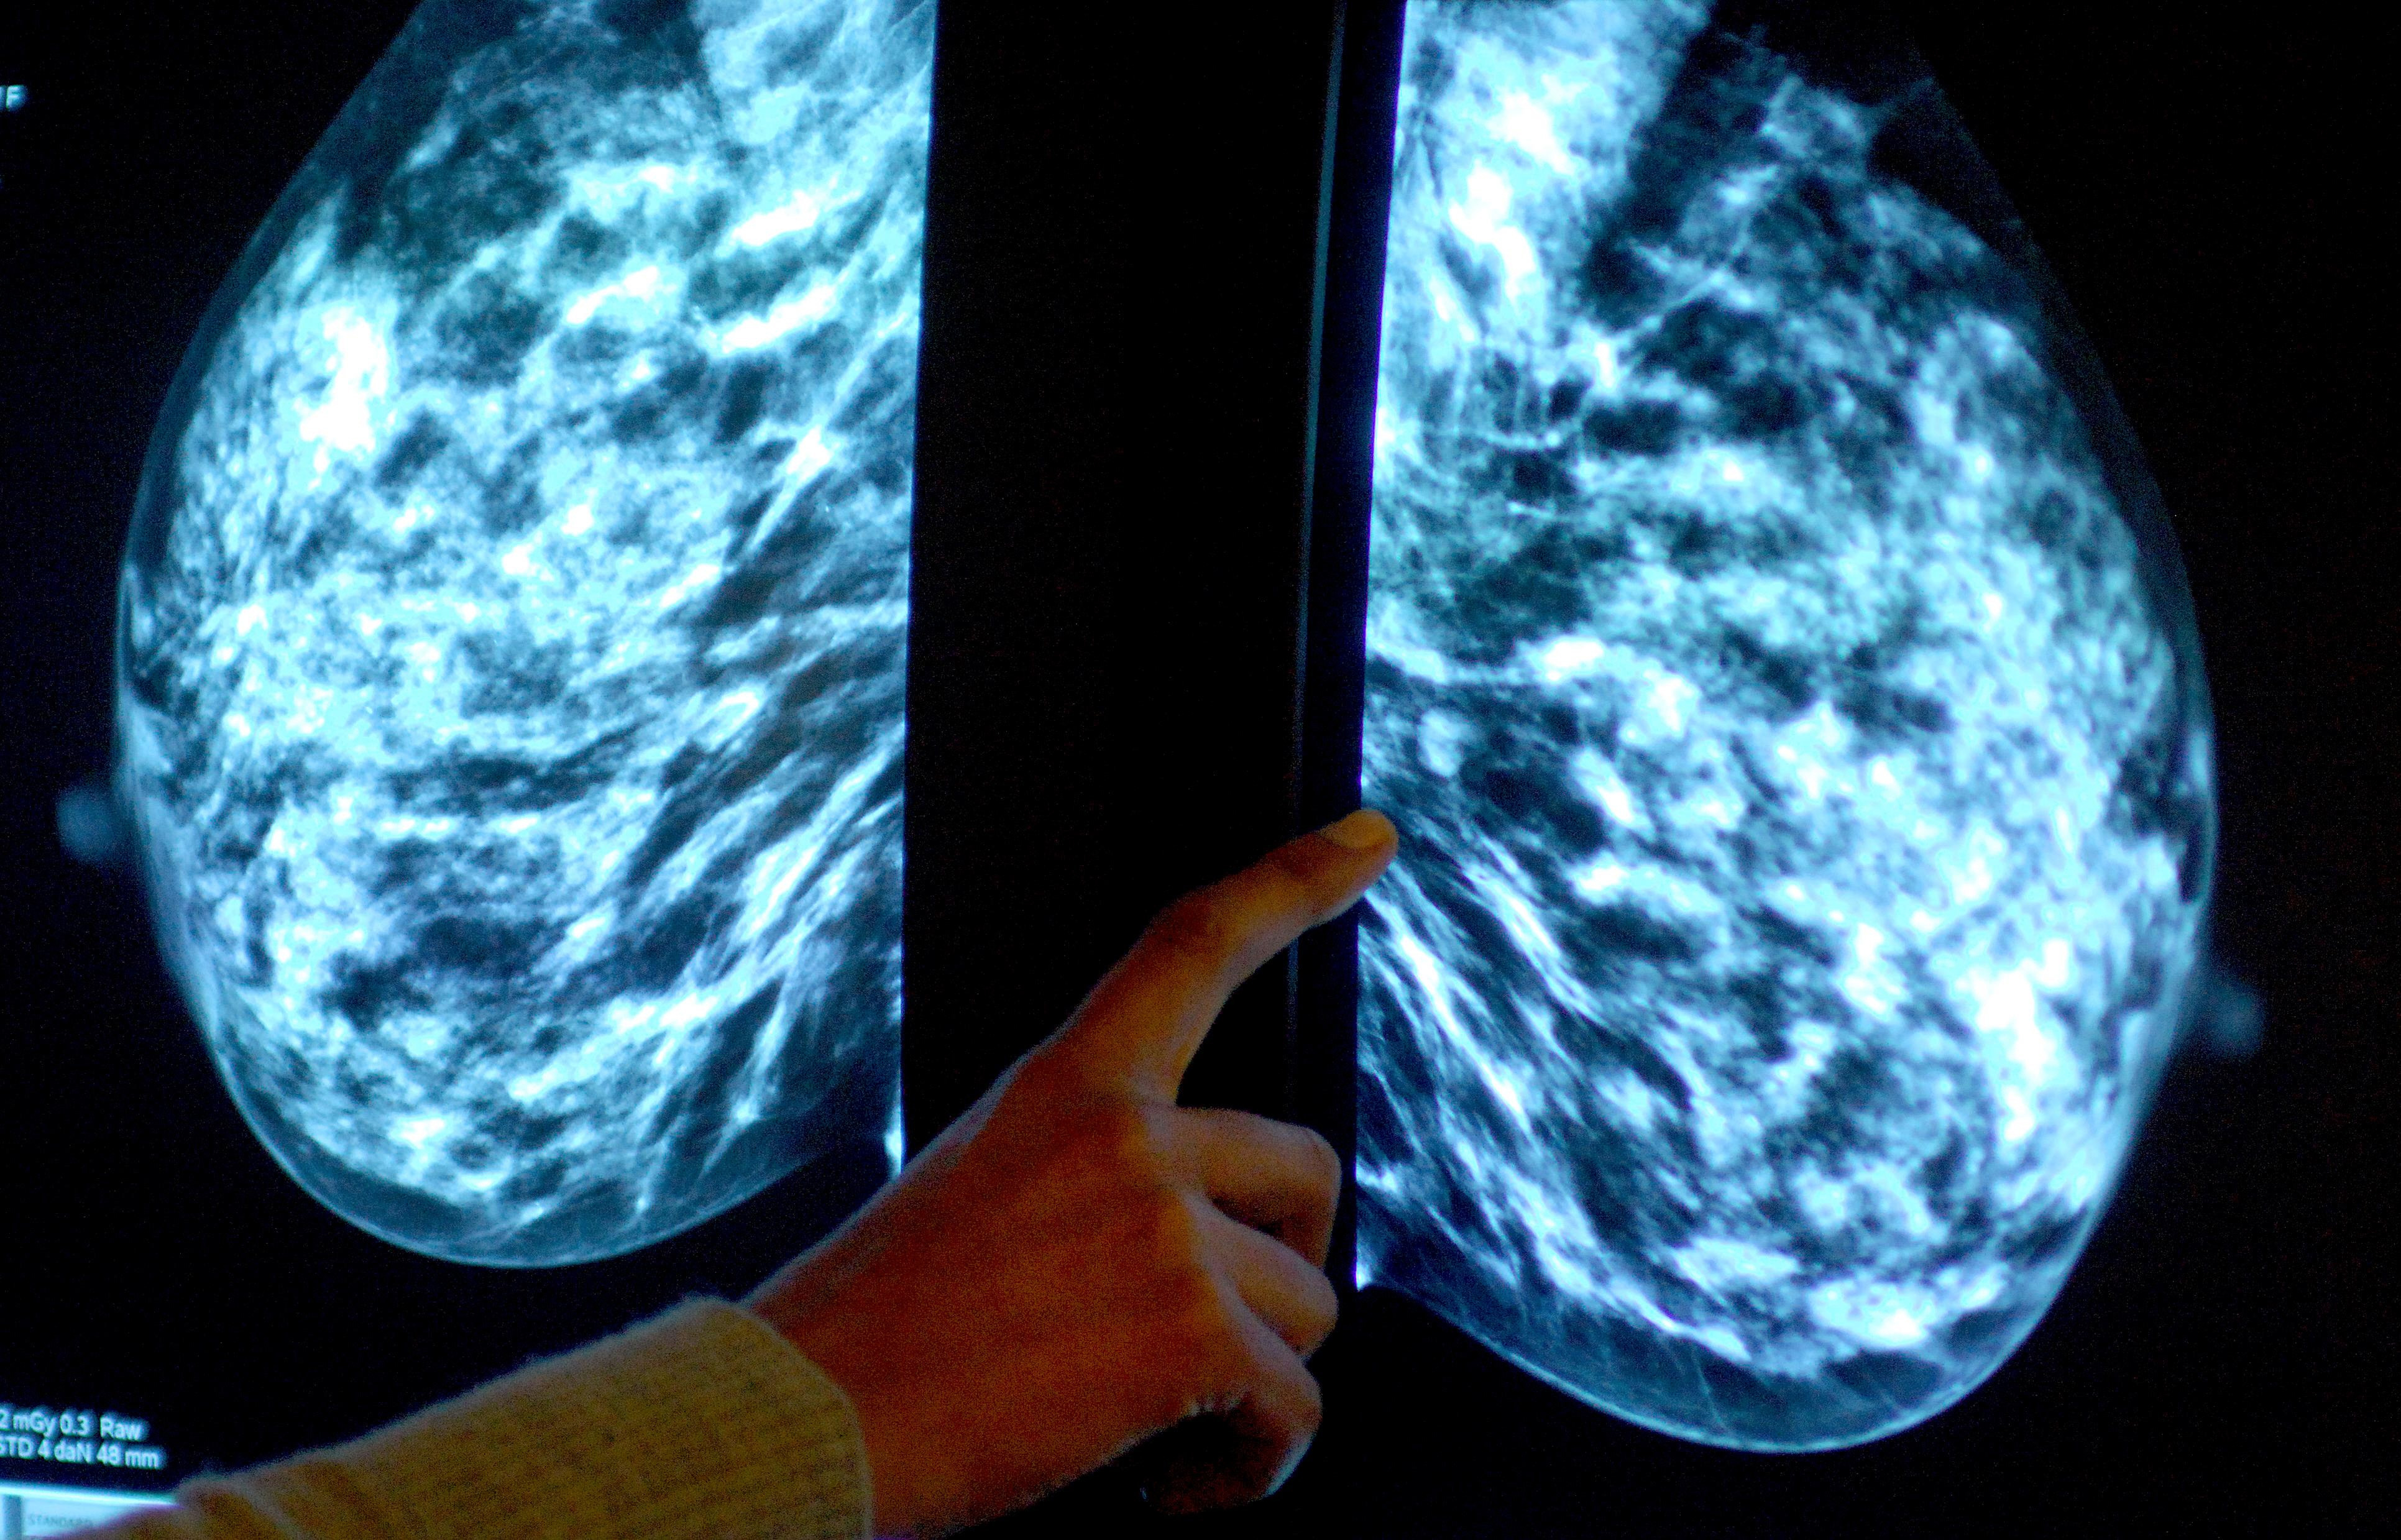

Breast screening uptake in Somerset remains below pre-pandemic levels, new figures show.

It comes as charities have said women still face too many barriers to regular testing, as fewer people in England underwent tests than before the coronavirus pandemic